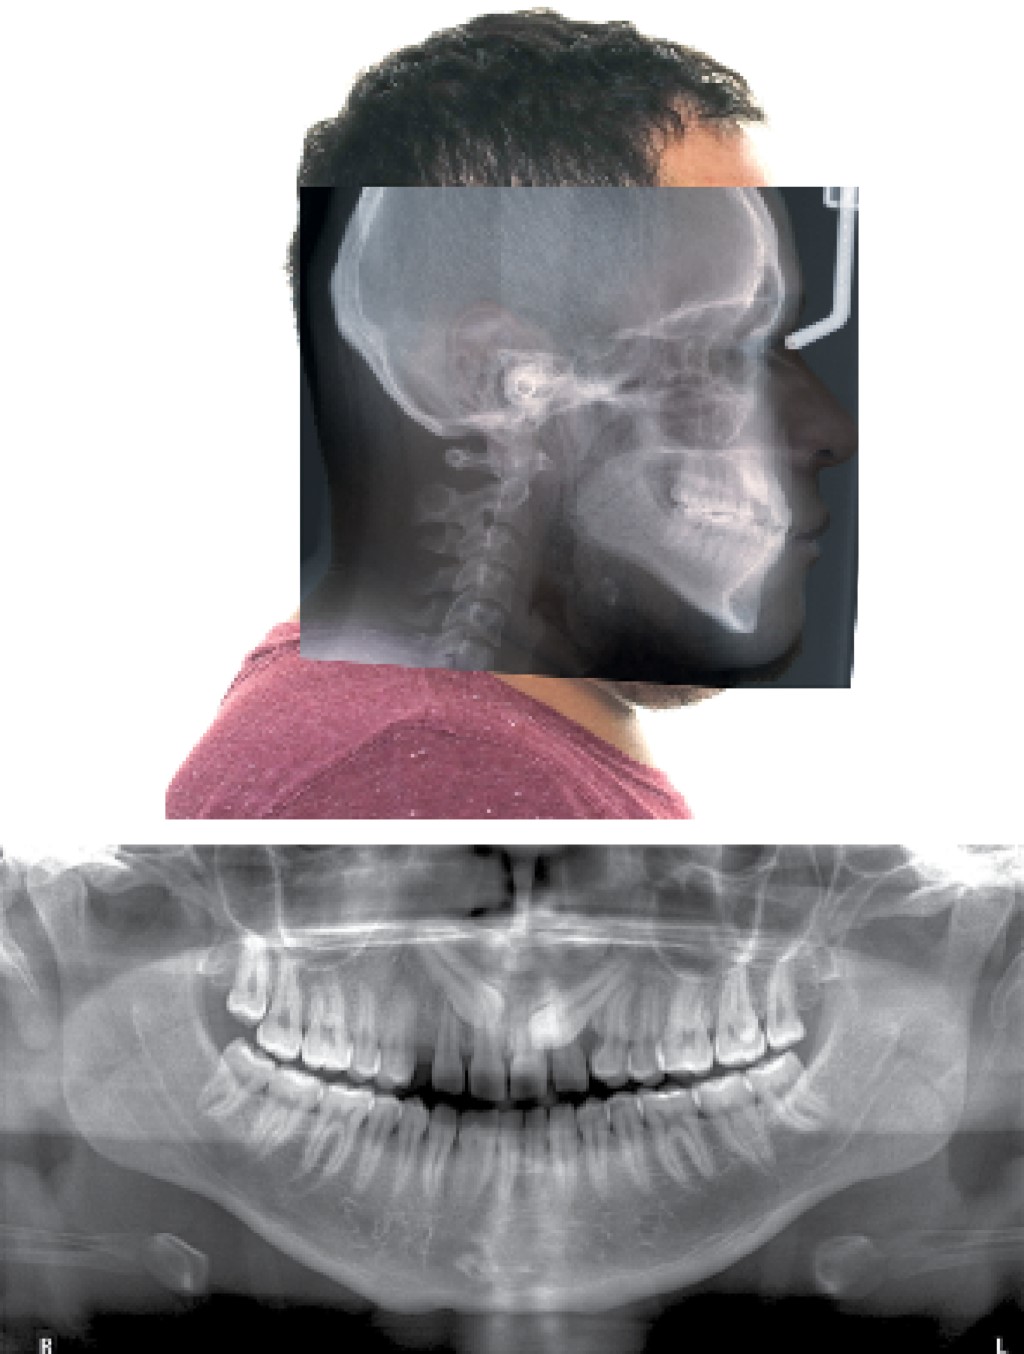

Al inicio, se tomaron registros clínicos para su análisis diagnóstico como fotografías de estudio extraorales e intraorales (Figura 1), modelos montados en articulador Panadent (PANADENT®, CA, EUA), radiografías, exploración física de articulación temporomandibular y exploración clínica para realizar análisis ortodóncico dental. Una vez realizada la toma de registros se realizaron las siguientes observaciones.

Aspectos esqueléticos: se observaron bases apicales coincidentes, un patrón general mesofacial, clase I esquelética, patrón dolicofacial del tercio inferior (Figura 2), inclinación dolicofacial del cuerpo mandibular con mandíbula mesofacial, pobre crecimiento sagital mandibular moderado, posterorrotación del cuerpo mandibular, una base craneal plana, posición normal moderada del maxilar, crecimiento vertical facial posterior en norma y alto potencial de crecimiento de la rama mandibular.

Figura 2